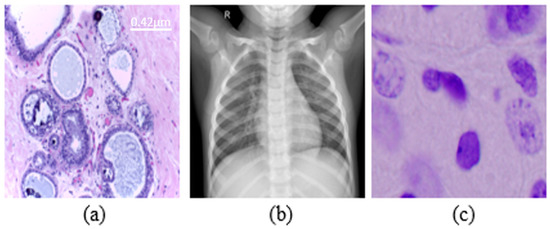

- Chowdhury, M.E.H.; Rahman, T.; Khandakar, A.; Mazhar, R.; Kadir, M.A.; Mahbub, Z.B.; Islam, K.R.; Khan, M.S.; Iqbal, A.; Emadi, N.A.; et al. Can AI Help in Screening Viral and COVID-19 Pneumonia? IEEE Access 2020, 8, 132665–132676. [Google Scholar] [CrossRef]

- Aresta, G.; Araújo, T.; Kwok, S.; Chennamsetty, S.S.; Safwan, M.; Alex, V.; Marami, B.; Prastawa, M.; Chan, M.; Donovan, M.; et al. BACH: Grand challenge on breast cancer histology images. Med. Image Anal. 2019, 56, 122–139. [Google Scholar] [CrossRef] [PubMed]